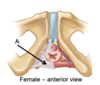

Name structures A-C of the pelvic diaphragm

A = levator ani

B = ischial spine

C = coccygeus